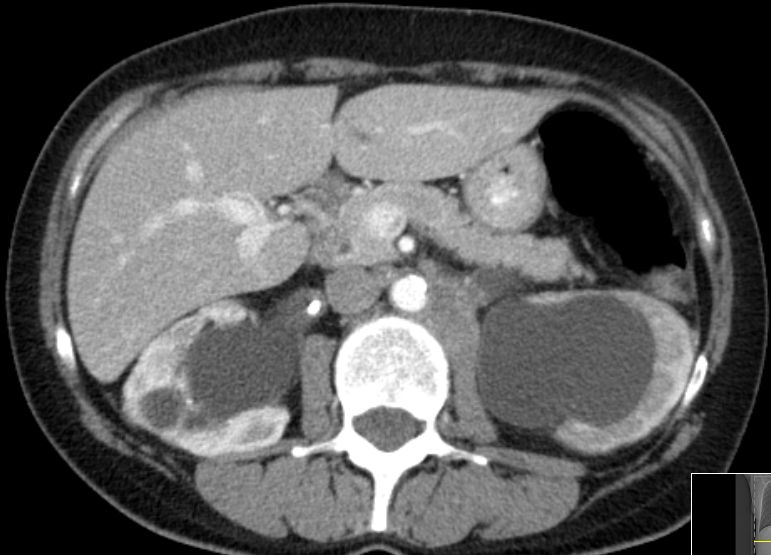

| paraaortale Lymphknoten - Metastasen |

![]() Großes Lymphknotenkonglomerat links paraaortal. Vergrößerte Lymphknoten an der linken Beckenwand. |

![]() 2 große Lymphknoten links zwischen Aorta und Musculus psoas. | ||